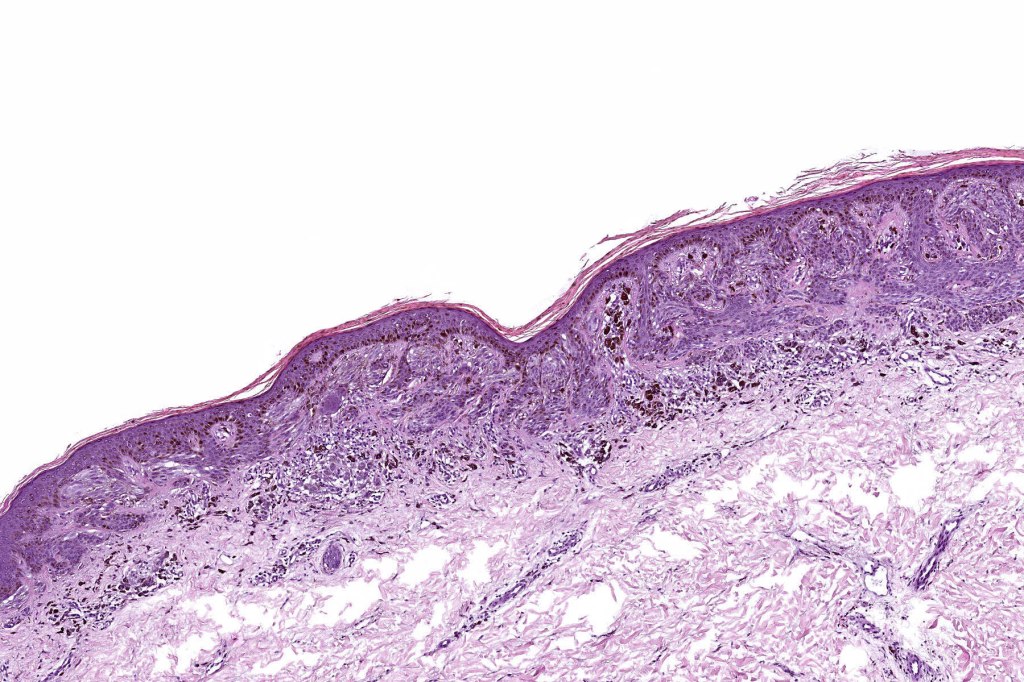

•Variant of Spitz nevus, readily identifiable at scanning magnification in the majority of cases

•Symmetrical and circumscribed with a characteristically flat lower border

•Vertically orientated oval junctional nests

. Heavy pigmentation although hypopigmented/amelanotic varinats can be encountered

•Junctional or compound

•Acanthosis & hyperkeratosis

. Lymphocytic infiltrate often seen at base